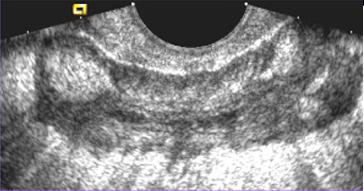

Aspect echographie percutanee c'est

image de epaissisement hyper-echogene de la paroi de

l'intestin par la fibrose sous-muqueuse et image

de spiculation hypo-echogene des vaisseaux droit et

image de stratification a la region lesionnaire du tube

digestif . .A la portion sclerosant ,

epaissisement de la paroi et le retresissement de la lumen de

l'intestin se voyait tres nette . Ulceration transmural parfois se voyait .